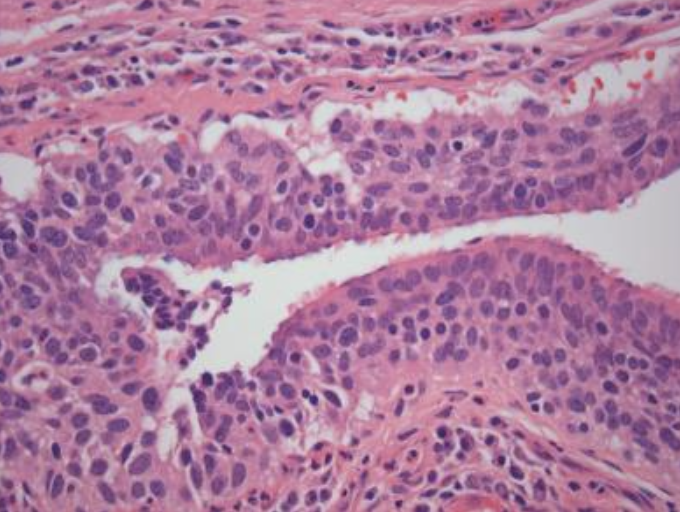

<p>Hiperplasia adenomatosa atípica</p>

Hiperplasia adenomatosa atípica

• Mide menos de 5mm

• Neumocitos displásicos

• Pared alveolar ligeramente fibrótica

• Paredes se engrosan